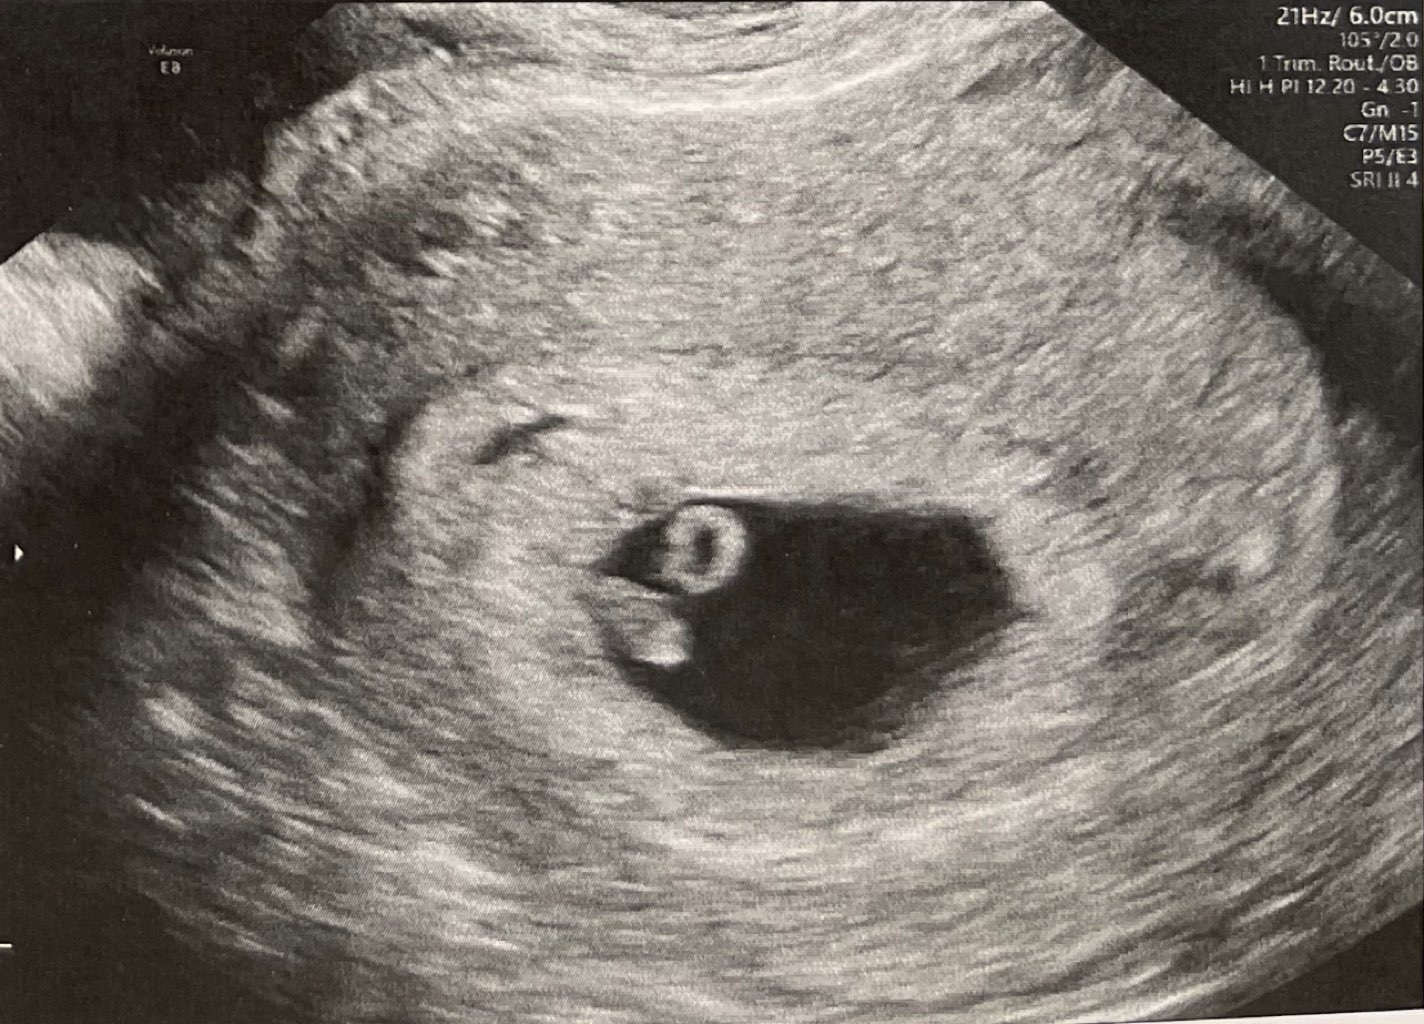

A wiec tak: jest serduszko! 124 uderzenia! 7mm fasolka, 6+4 (z okresu było 7+3! - dużo młodsza!) termin na 18.03!